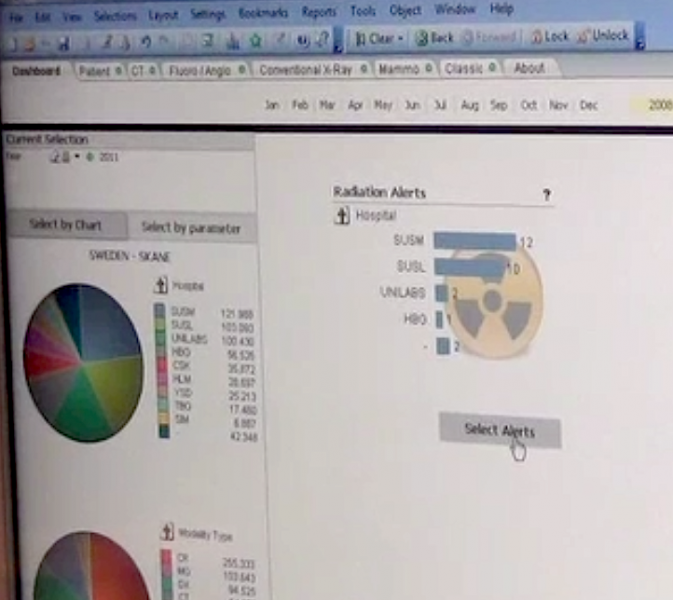

Patient X-ray radiation exposure from medical imaging has been a hot topic in radiology and has prompted the implementation of radiation dose monitoring systems. Prior to these systems, dose measurements either were not tracked or required manual calculation of dose based on scanner data in the DICOM headers.

Philips PerformanceBridge Practice dashboard, developed on the HealthSuite digital platform, offers at-a-glance insights into uptime, operations and performance across your imaging equipment. The dashboard also provides actionable recommendations, case studies and training alerts.